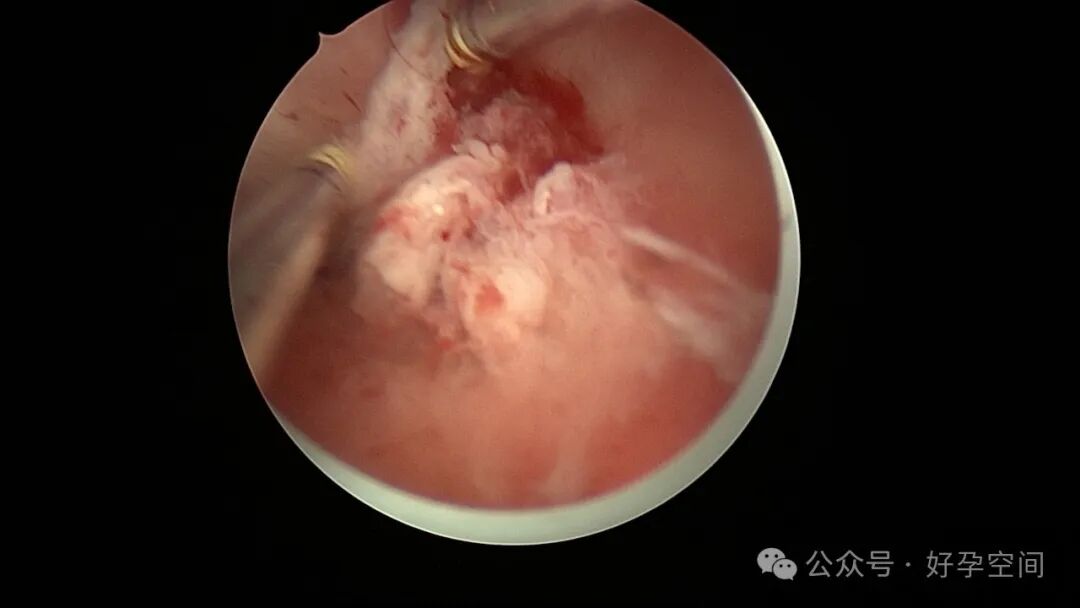

病例1:32岁,G8P3,剖宫产3次,本次停经50+天,计划外妊娠,宫腔镜辅助下清宫,见剖宫产瘢痕憩室,宫腔后壁2.5cm*2.0cm组织难以清除,宫腔镜电切送病检,病检结果为宫腔妊娠组织。

病例2:32岁,G3P1,剖宫产1次,本次停经60+天,稽留流产,宫腔镜辅助下清宫,宫腔广泛粘连,单极电针分粘。术后19天宫腔镜二探,宫腔后壁见1.0cm*1.0cm组织凸起,宫腔镜电切送病检,病检结果为宫腔增殖期样子宫内膜,另见血凝块及纤维素样坏死组织,浅肌层内可见少许滋养叶细胞(病理医生曾与临床医生沟通,病理图片跟超常胎盘部位反应很相似,但最后仅给出了以上病检诊断)。

病例3:26岁,孕产史不详,本次停经60+天,稽留流产,宫腔镜辅助下清宫,见剖宫产瘢痕憩室,左侧宫角2.0cm*1.5cm组织凸起,难以清除,宫腔镜电切送病检,病检结果为蜕膜组织及平滑肌组织。

病例4:34岁,G3P1,顺产1次,本次停经40+天,计划外妊娠,宫腔镜辅助下清宫,宫腔前壁2.cm*1.0cm组织难以清除,家属拒绝切除送病检,术后2周复查B超,宫腔查见1.1cm*1.0cm占位,无血流信号,门诊随访。